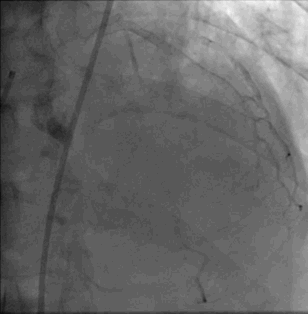

确认冠脉风险

冠脉高度尚可,冠脉平面无可见瓣叶

对侧距离大于30

确认冠脉情况

球囊预扩

大小球囊依次预扩